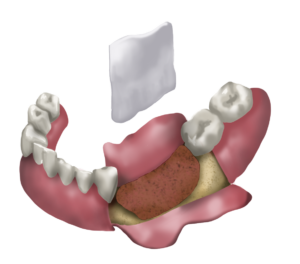

PRÒTESIS

A La Clínica Verda no utilitzem metalls en les pròtesis que col·loquem. Prioritzem materials nobles i molt resistents com el Zirconi, el Disilicat de liti o la porcellana. Materials que confereixen una gran estètica però també una gran resistència sense cap mena de toxicitat per l’organisme.

Sempre que fem una rehabilitació protètica reequilibrem la boca segons els principis d’equilibri i funció òptims preconitzats per la rehabilitació neuro-oclusal, basada en un estudi minuciós de les conseqüències posturals i osteopàtiques de l’encaix de les dents i dels moviments a l’hora de mastegar. D’aquesta manera ajudem al consultant a mantenir o retrobar i millorar el seu equilibri.

CIRURGIA DE REGENERACIÓ ÒSSIA

A la Clínica Verda utilitzem una tècnica pròpia en la qual s’extreu sang venosa del consultant en un vial sense anticoagulant, de tal manera que al cap de 30 minuts obtenim un coàgul semi sòlid que trossegem i combinem amb un complex mineral provinent del corall marí (de cultiu, no extret de barreres de corall naturals).

Un cop fet això, col·loquem aquest preparat dins d’un foil de titani que ens servirà de sostén i de motlle per regenerar els teixits ossis i gingivals perduts per el procés natural d’envelliment que es produeix quan es perden les dents.

Si la pèrdua òssia és molt gran fem un disseny 3D del maxil·lar i el regenerem utilitzant la mateixa tècnica de sang autòloga i corall però ens servim de l’última tecnologia mitjançant la qual tenim un motlle de titani liquat que reprodueix la forma original de l’os facial.

Un cop tenim l’os suficient, ja podem col·locar implants i pròtesis sobre implants per rehabilitar la mossegada i l’òptima funció de la boca.

L’avantatge d’aquesta tècnica, en la que s’utilitza sang autòloga, és que no introduïm en l’organisme productes d’origen animal, de cadàvers humans o sintètics, sinó que son les pròpies cèl·lules mare que trobem en la sang del consultant que transformaran el coàgul en os i geniva.